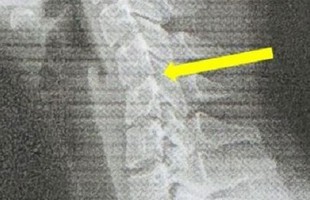

Cô gái 20 tuổi sở hữu cột sống cổ của người 60 vì nghiện chơi game